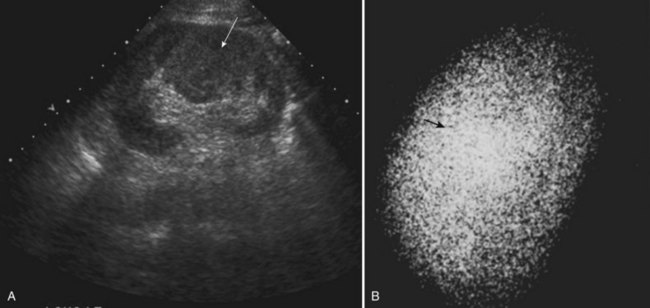

A number of normal variants of the pyelocalyceal system in the kidney have been described. One such entity manifests as a localized mass, usually situated between the infundibula of the upper and middle calyces, and is called a hypertrophied column of Bertin (Fig. 117–22). The column may be sufficiently large to compress and deform the adjacent pelvis and calyces, suggesting a mass or “pseudotumor.” The individual calyces, however, are normally shaped and developed.

Figure 117–22 Column of Bertin. A, Ultrasonogram shows sagittal view of left kidney and possible midpolar mass. B, DMSA scan demonstrates normal uptake in the area of the mass (arrow), suggesting the pseudotumor, but it is actually a hypertrophied column of Bertin.

(A, Courtesy of Dr. Shpetim Telegrafi.)

It is important to differentiate this calyceal anomaly from true disease of the calyx and from a parenchymal tumor. A renal ultrasound study shows a normal echogenic pattern of parenchyma in the area in question, and a renal scan shows normal uptake of the radioisotope in this area (Parker et al, 1976).